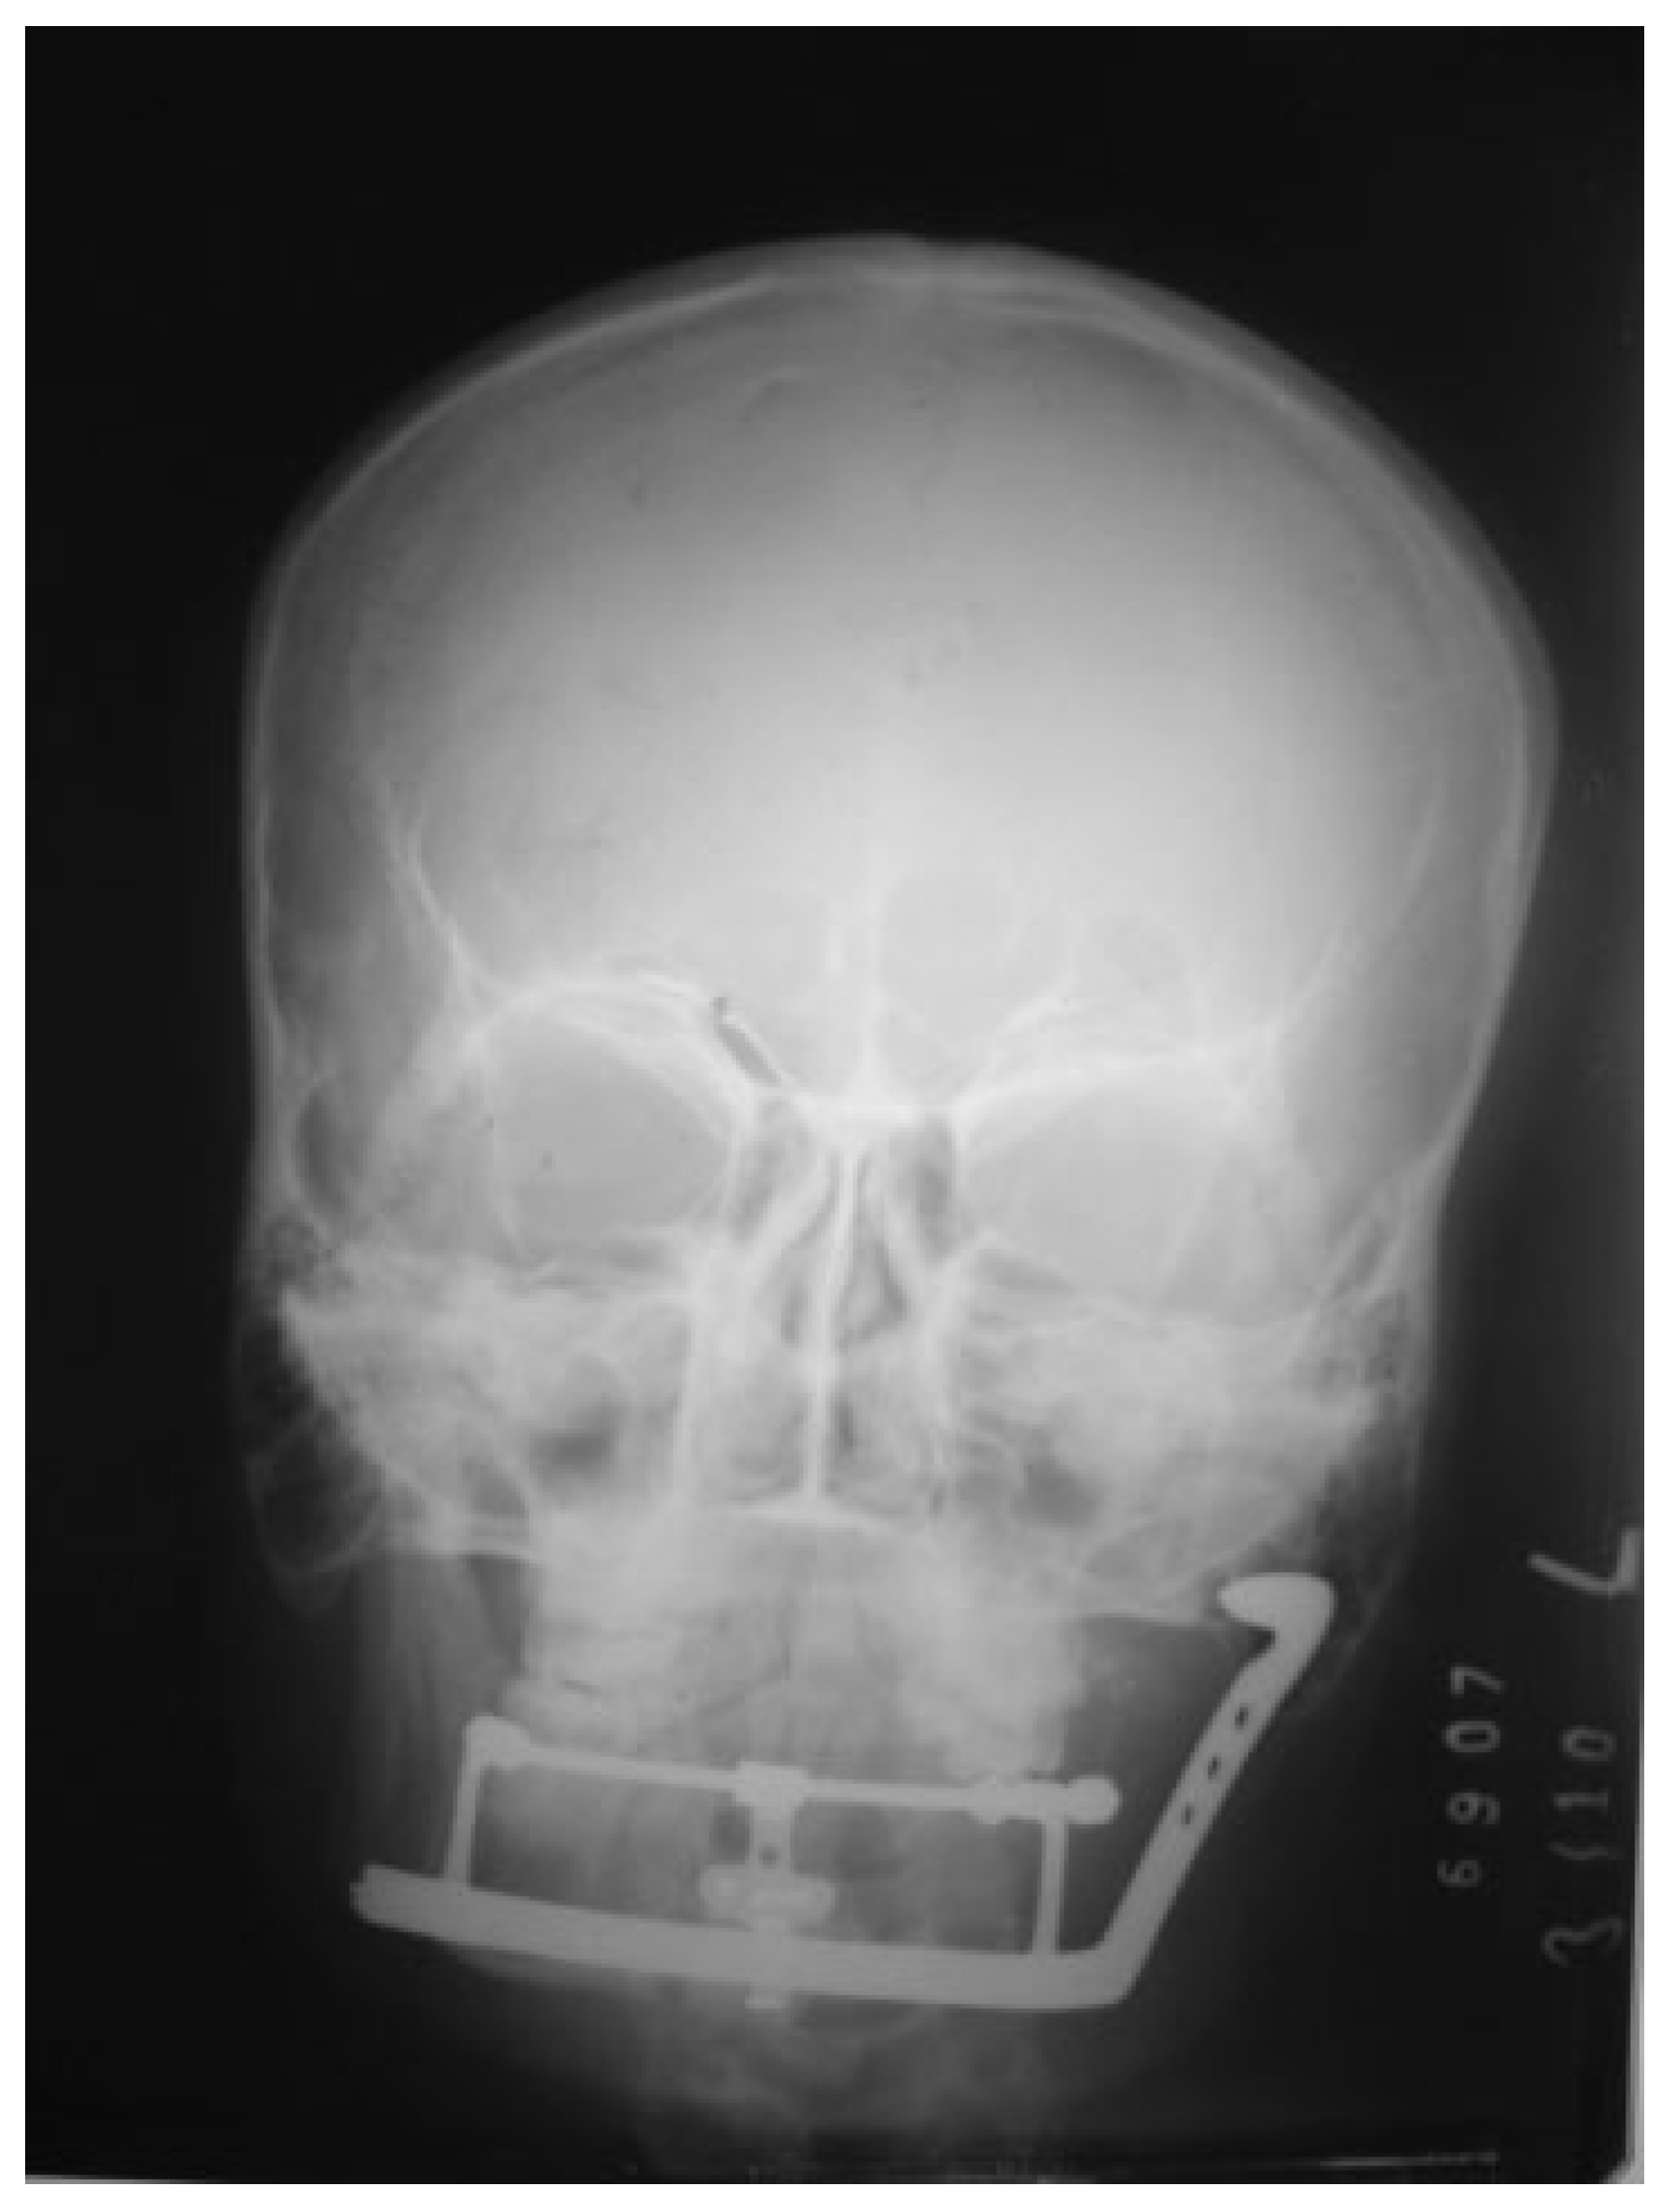

Figure 12.

A frontal skull view radiograph showing the device present.